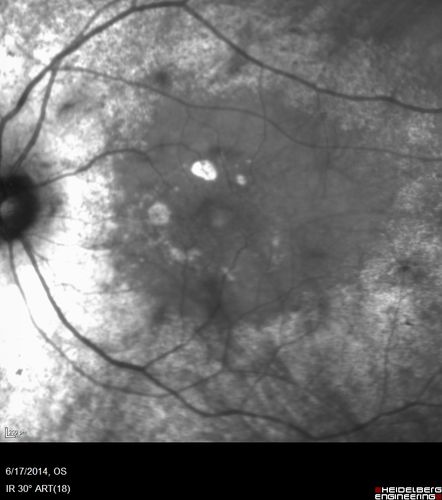

Retinitis Pigmentosa - RP1 Mutation

78 year old man: 20/32 OD and 20/50 OS - RP1 Gene is Bad -- > RP with Novel Amino Acid Change in GLY723Stop sequence of the RP1 gene - consistent with AD RP